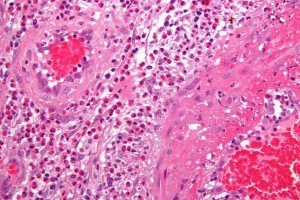

Механизм развития изолированного ЦВ не установлен. Морфологически в сосудистой стенке выявляются инфильтраты (скопления одноядерных клеток), наблюдается формирование гранулём. Вторичный церебральный васкулит при системных сосудистых и ревматических заболеваниях имеет аутоиммунный патогенез: сосудистая стенка повреждается антителами, вырабатывающимися к её элементам вследствие неадекватной реакции иммунной системы.

В остальных случаях воспалительный механизм запускается прямым воздействием этиофактора (токсинов, бактерий, вирусов). Воспаление сосудистой стенки приводит к её истончению, сужению сосудистого просвета, повышенной проницаемости.

Для изолированного церебрального васкулита, характерно образование уплотнений и воспалительных узелков на стенках сосудов. Для вторичного – сбой в иммунной системе и поражение стенок сосудов защитными антителами или непосредственное воздействие вирусов.

Диагностирование на начальной стадии заболевания, может не выявить нарушений в головном мозге. Для подтверждения диагноза прибегают к биопсии церебральной паренхимы – забор материала проводится только из мелких артерий.